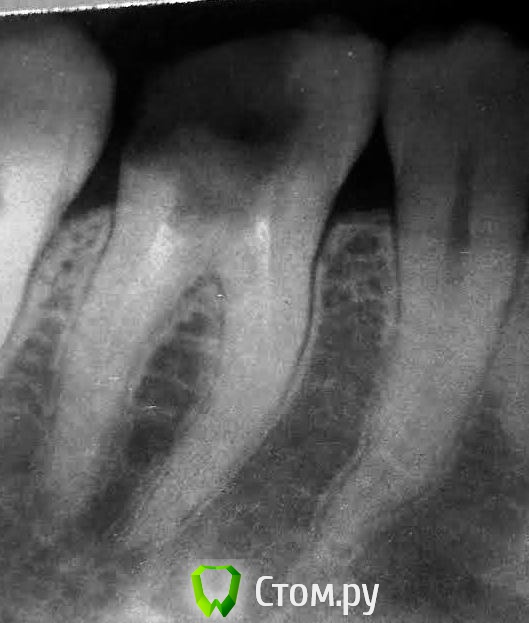

sunbeam Опубликовано 3 июля, 2014 Автор Поделиться Опубликовано 3 июля, 2014 Добрый день, прикрепляю прицельный снимок 3.6 и фото, насколько его удалось сделать. Врач предложила перепломбировать каналы и восстановить зуб пломбой.В моем представлении такой большой зуб пломбой восстановить несколько ненадежно,нужен по крайней мере штифт, чтобы пломба не отвалилась из-за мармеладки, как в прошлый раз. Так как я не специалист, очень хотелось бы мнений. Ссылка на комментарий

red_butler Опубликовано 4 июля, 2014 Поделиться Опубликовано 4 июля, 2014 Перелечить корневые каналы, далее корневая вкладка и коронка. И откладывать уже не куда 1 Ссылка на комментарий

IvanK Опубликовано 4 июля, 2014 Поделиться Опубликовано 4 июля, 2014 + 1 , еще чуть-чуть и на удаление Ссылка на комментарий